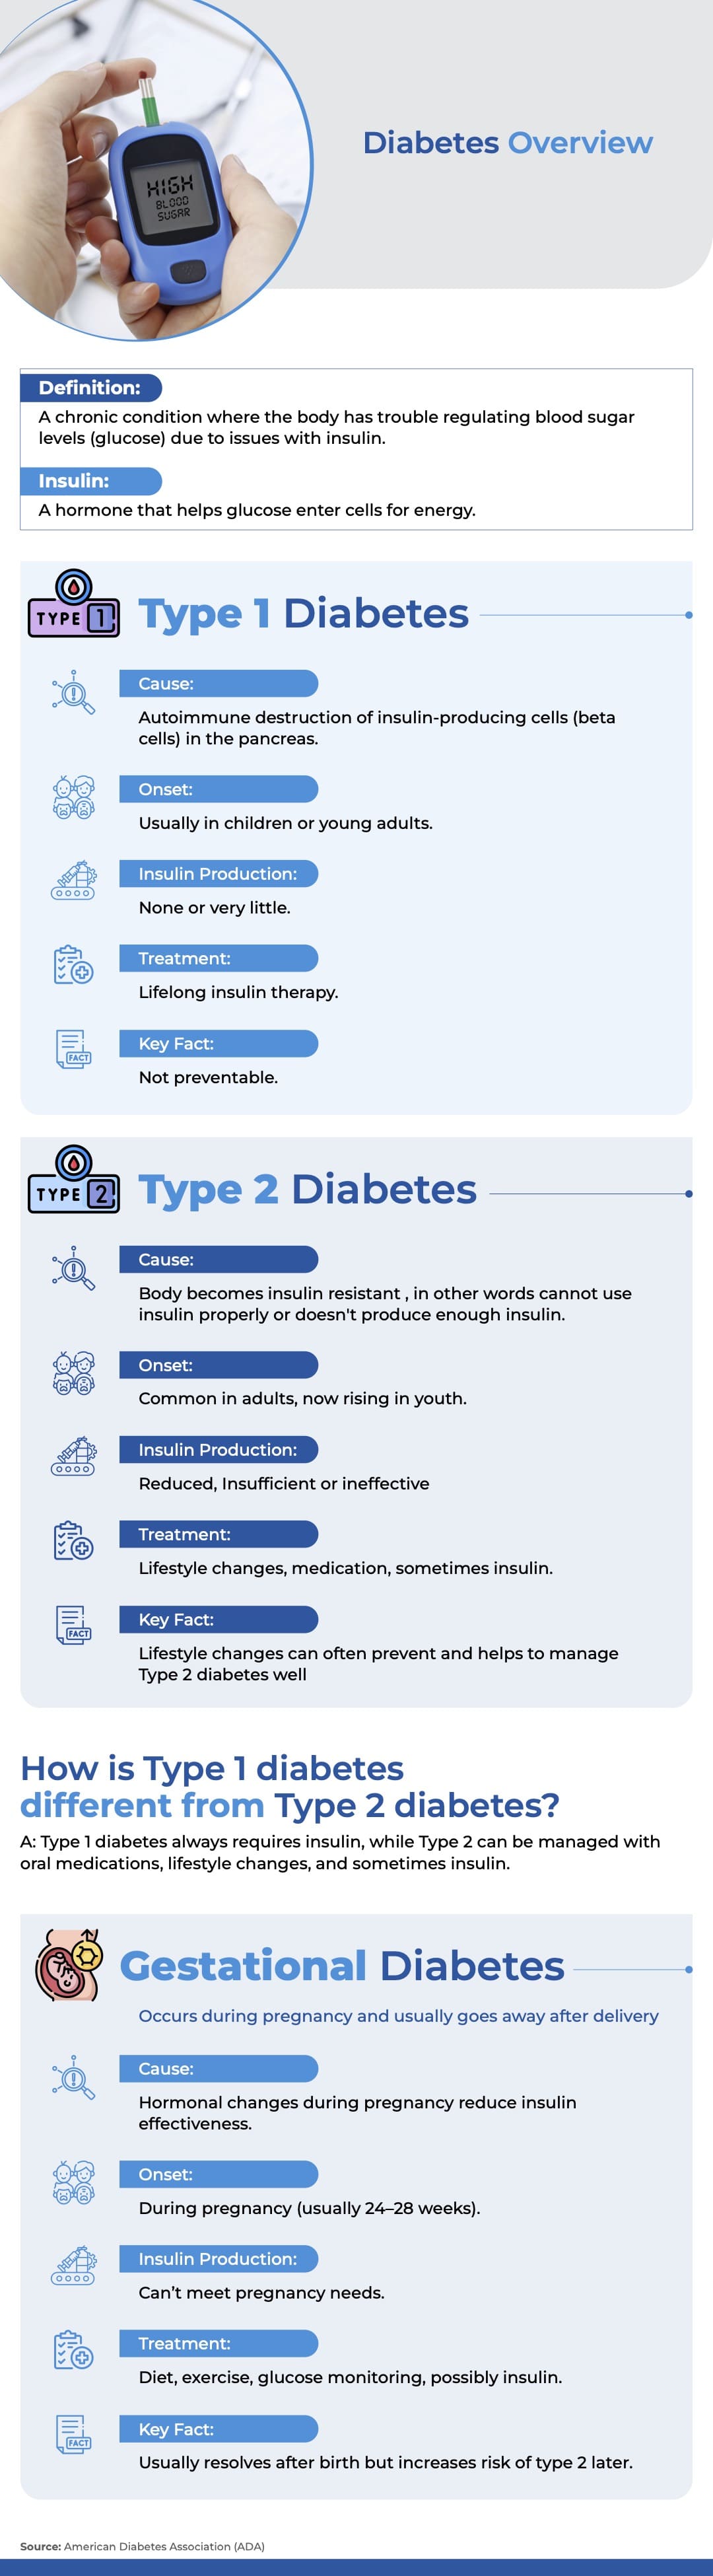

Diabetes Management

Diabetes Overview